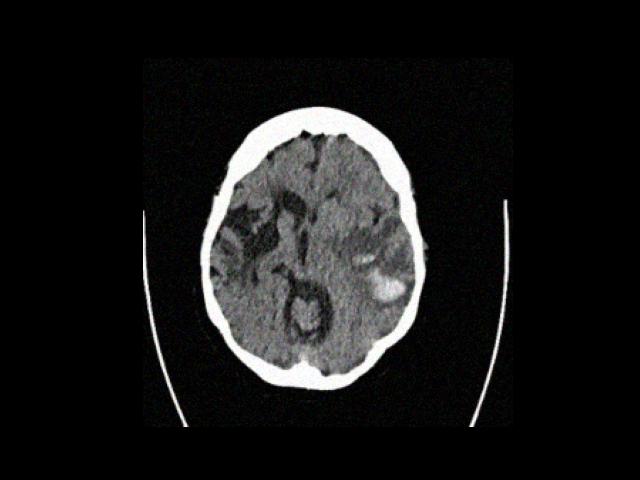

Sample Gallery